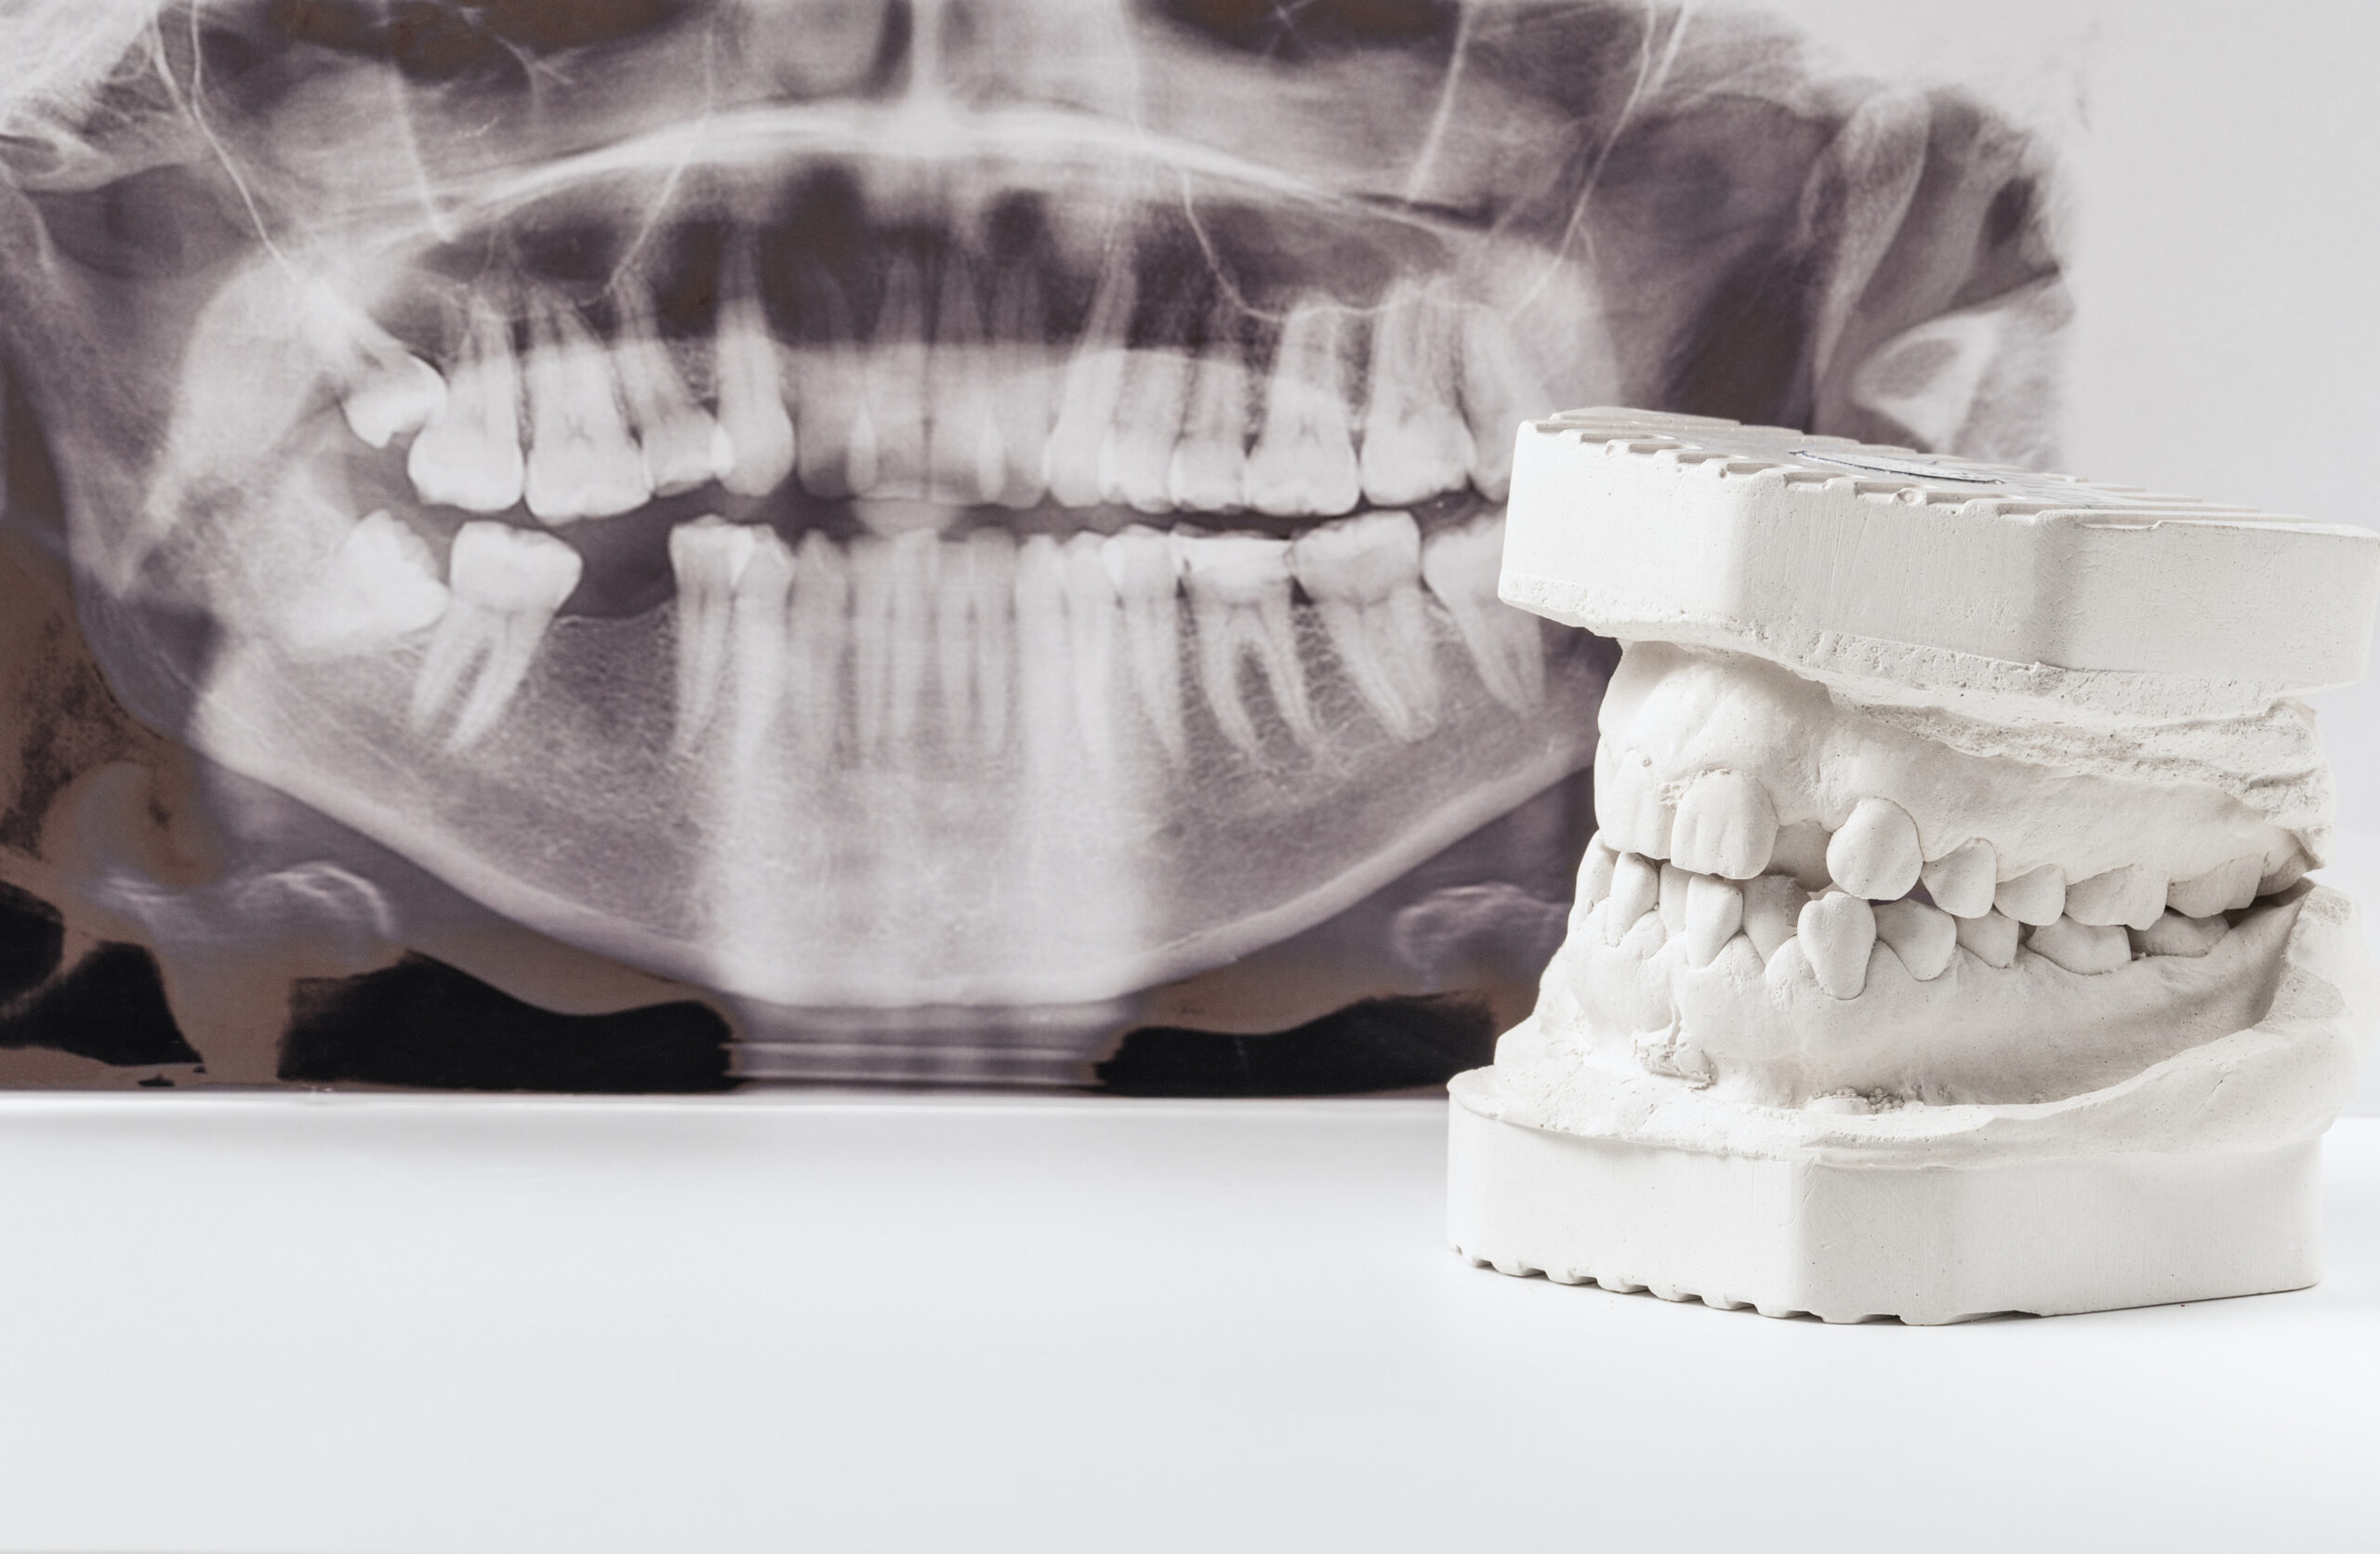

- Panoramic: The most common type of dental X-ray is the panoramic, which takes images of your entire mouth from front to back. It can show the position of fully emerged, emerging, and impacted teeth in one image, making it essential for checking cavities, wisdom teeth, and other dental problems.